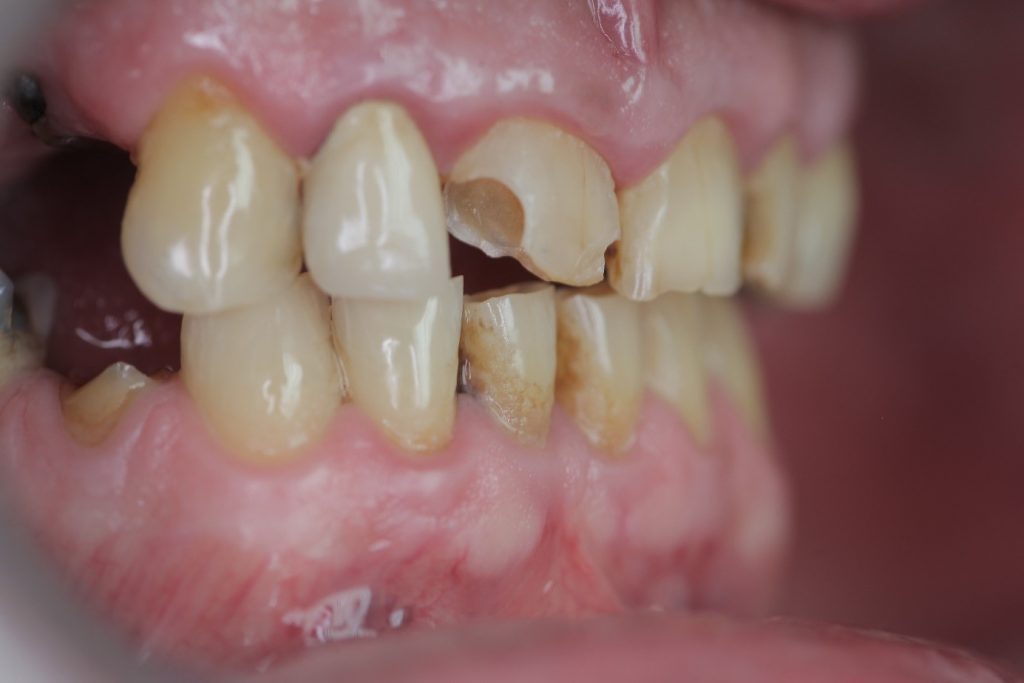

Multiple front teeth fillings, edge restorations using Asteria composite (Case presentation) (54)

A male patient, aged 67, reported to our clinic with the aim of having his condition assessed. He received a detailed treatment plan for his dental problems, which meant the fabrication of a full-arch bridge for his upper jaw. During the patient’s 2-day stint in Hungary we tried to focus on dealing with the most critical problems.

The front teeth were filled using Tokuyama Asteria Estelite filling materials.